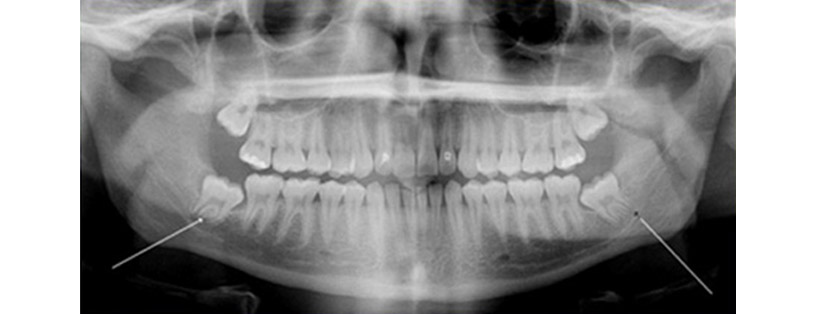

Οι σωφρονιστήρες (φρονιμίτες) είναι τα δόντια που συχνότερα παραμένουν έγκλειστα ή ημιέγκλειστα λόγω ανεπαρκούς χώρου στον οδοντικό φραγμό. Στους περισσότερους ανθρώπους εμφανίζεται γύρω στην ηλικία των δεκαέξι ετών και είναι το τελευταίο δόντι που συμπληρώνει τη φυσική οδοντοστοιχία. Συχνά το δόντι αναπτύσσεται σε ανώμαλη θέση χωρίς να αναδυθεί στη στοματική κοιλότητα βάζοντας σε κίνδυνο τα γειτονικά ανατομικά μόρια.

1. Πριν την επέμβαση χορηγείται τοπική αναισθησία. Είναι μία σχετικά επίπονη διαδικασία, καθώς ο ασθενής είναι αναγκασμένος να διατηρεί το στόμα όσο το δυνατόν πιο ανοιχτό λόγω της θέσης του δοντιού στο βάθος του στόματος. Πριν την επέμβαση συνήθως απαιτείται η λήψη ακτινογραφίας.